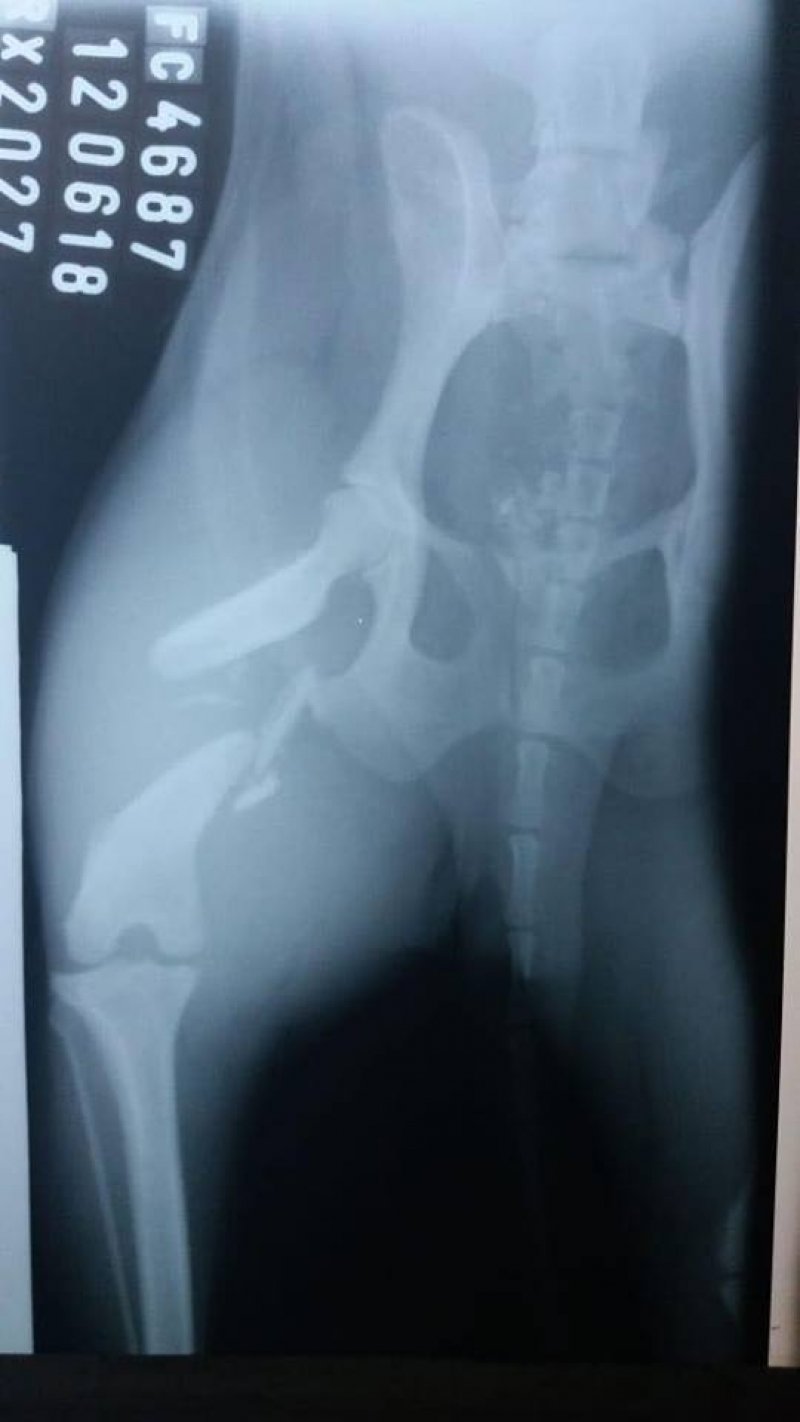

Colabore com a cirurgia da Belinha

Belinha foi salva por uma protetora e doada para uma familia no dia 1º do mês passado. Ela ‘fugiu’ no mesmo dia e uma pessoa informou que a ‘menina’ havia sido atropelada em frente a um posto de combustíveis, no bairro São João Margem Direita, dois dias depois. Desde o seu sumiço ocorreu uma mobilização para encontrá-la. No último dia 12, ela foi levada ao veterinario, feita uma radiografia e constatado uma fratura completa em espiral na pata direita. A situação é delicada. Essa ‘guerreira’ tem tomado remédios para dor. Agora, ela está em Criciúma e é necessário arrecadar dinheiro para o tratamento. Ainda não se sabe o valor total, mas até o momento o custo foi de R$1.1. Acredita-se que o montante final do tratamento será de R$1.7. Além disso, há os custos com as medicações e toda a recuperação. Quem puder ajudar entrar em contato com a Simone pelo telefone 48- 99191-9137. Qualquer valor ajuda muito, se cada um doar um pouquinho no final teremos o montante completo. Muito obrigada!